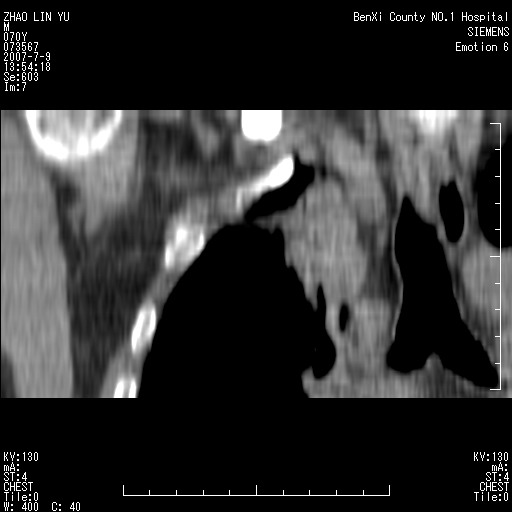

以下是引用王靖旗在2007-7-10 17:12:00的发言:[br] 男、70、咳嗽两个月,半年前换瓣手术,胸片未见异常,于昨天行x片发现右肺上野大片影,行ct扫描,这里是减薄图像,余肺正常。明天晚上会有增强扫描片,到时我会上传。[br][br] 冠状位请大家细看,应该是有意义的,[br][br] 请大家先看平扫发表意见。[br][br]

[br]冠状面[br]